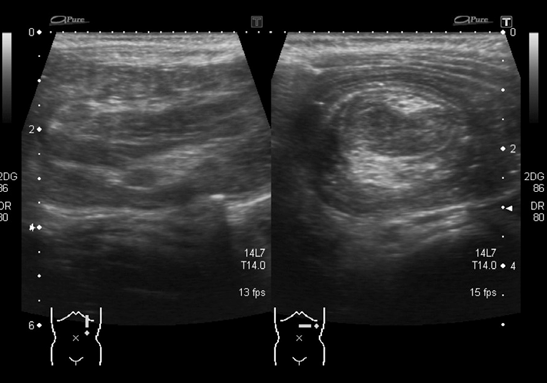

Fig. 56.3

Reducción neumática que muestra con mayor claridad la intususcepción en el lado izquierdo (flecha).